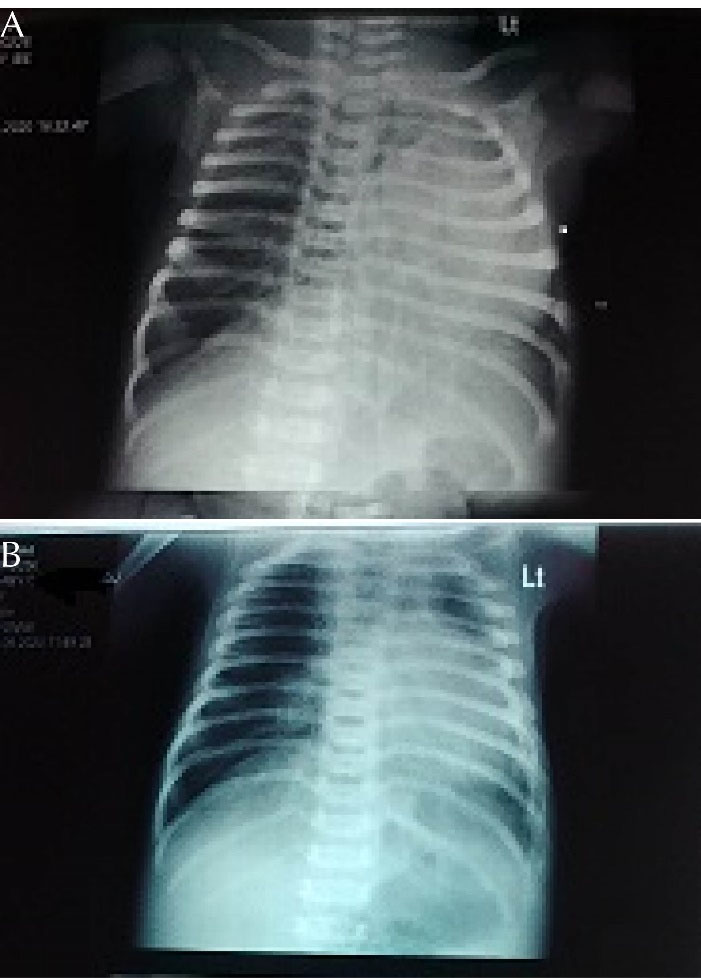

He was commenced on intranasal oxygen and subsequently placed on continuous positive airway pressure, intravenous fluid and intravenous antibiotics. The chest radiograph showed left lung collapse from possible left main bronchus obstruction and compensatory hyperinflation on the right lung (). A 2D Echocardiography showed moderate tricuspid regurgitation, pulmonary artery pressure of 30mmHg with a right-to-left shunt through a patent foramen ovale and left atrial dialatation

There was a significant improvement in the respiratory distress by the 3rd day following commencement of these medications. The SpO2 improved from 72% to 96% while the respiratory rate reduced from 90 cycles/min to 62 cycles/min. A repeat 2D ECHO done two weeks after initiation of oral sildenafil showed a reduction in the pulmonary artery pressure to 20mmHg. While repeat chest radiograph showed improvement in the lung markings (). The baby was subsequently weaned off CPAP and continued on intranasal oxygen for few days before oxygen was discontinued. The baby was discharged home with follow up at both the Neonatology and Cardiology clinics.

Figure 1. (A): Chest radiograph showing left lung collapse, (B): improvement in lung markings after commencement of oral Sildenafil